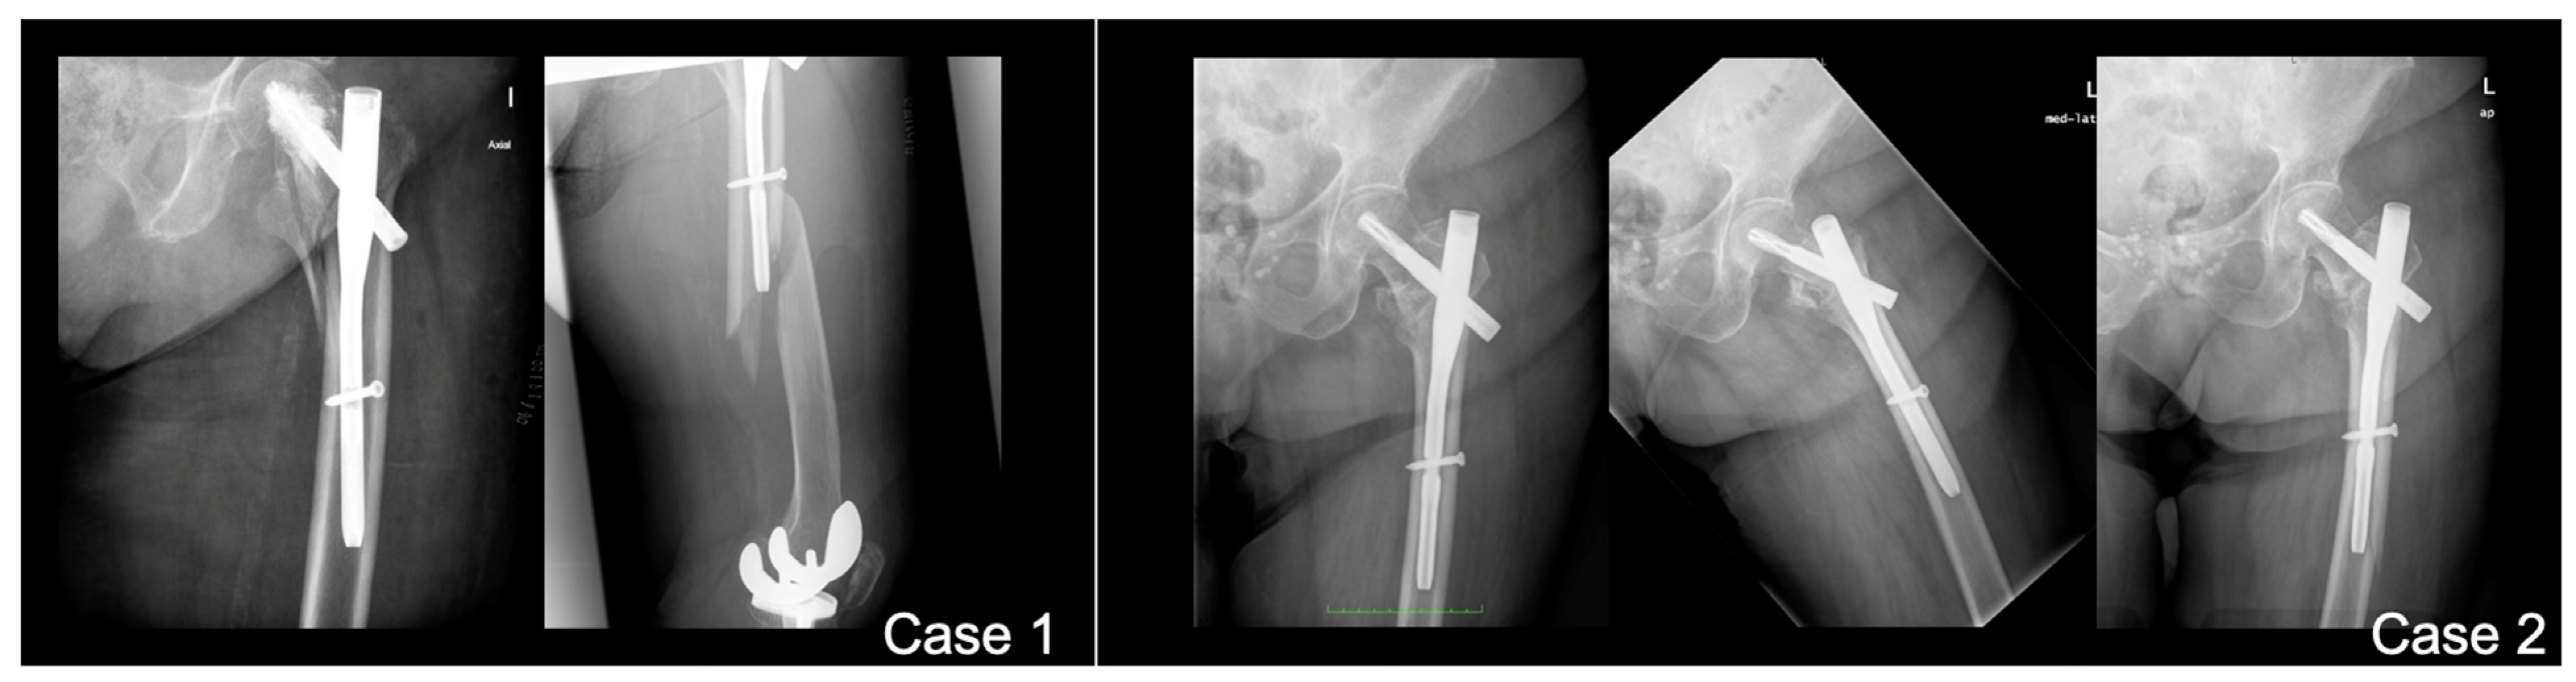

With 26.4% of patients experiencing fractures within 2 months post surgery of the index fracture, we advise a careful surgical technique to further improve outcomes and minimize the risk of PIFFs. The following strategies can be adopted. Surgeons should avoid overtightening distal locking screws against the outer cortical bone of the femur. Utilizing short femoral nails that do not impinge upon the anterior cortical bone (or considering the use of anatomical left and right nails) can also be beneficial. Employing overlapping techniques when other implants are present in the femur is advisable, while preventing the errors and outcomes presented in Figure 4, Figure 5 and Figure 6. Furthermore, using protective medications for bone fragility, such as anti-resorptives, following the diagnosis of an initial fracture (index fracture) may enhance patient outcomes.

Figure 5. Error #2—improper overlapping. When a type C fracture is present, the original implant should be retained if possible to protect the femoral neck. In such cases, the use of a distal retrograde plate with overlapping is recommended. For enhanced protection, the overlapping should extend as proximally as possible. To improve fixation, various implant options are available, including periprosthetic plates, periprosthetic screws, variable-angle plates, and locking attachment plates, among others.